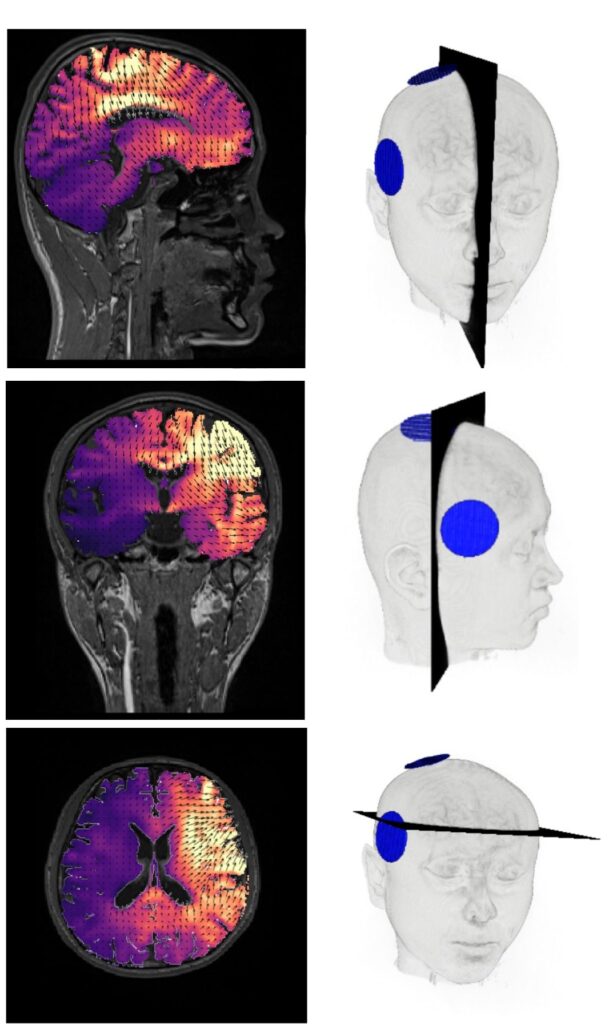

Hoe ziet ECT eruit op een hersenscan?

Deze afbeeldingen laten zien hoe het elektrische veld in de hersenen werkt. Bij het plaatsen van de elektrode aan de rechterkant (RUL) stroomt de elektriciteit van de bovenste elektrode naar de onderste. De lichte gebieden laten zien waar de stroom is.

Hier ziet u het elektrische veld in de hersenen. Dit zijn simulaties, gebaseerd op een MRI-scan. Het is geen persoon die echt ECT heeft gehad.

Hier ziet u hoe de stroom van de bovenste elektrode naar de onderste beweegt. De pijlen laten de richting zien, en de kleuren geven aan waar de meeste elektriciteit is.

Het meeste van de elektriciteit gaat dus door de rechterkant van het hoofd.

Dit zijn datasimulaties, gemaakt van een MRI-scan. Het is dus geen persoon die daadwerkelijk ECT heeft gekregen.